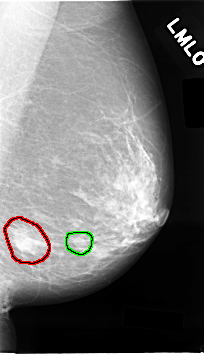

C_0024_1.LEFT_MLO

FILE: C_0024_1.LEFT_MLO.OVERLAY

TOTAL_ABNORMALITIES 2

ABNORMALITY 1

LESION_TYPE MASS SHAPE N/A MARGINS ILL_DEFINED

ASSESSMENT 5

SUBTLETY 5

PATHOLOGY MALIGNANT

TOTAL_OUTLINES 1

BOUNDARY

ABNORMALITY 2

LESION_TYPE MASS SHAPE OVAL MARGINS CIRCUMSCRIBED

ASSESSMENT 3

PATHOLOGY BENIGN